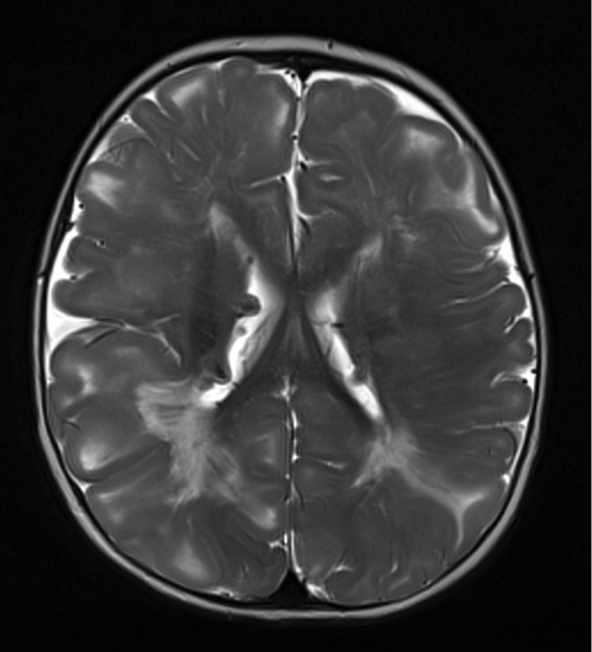

Imaging in tuberous sclerosis

The image below is a T2-weighted image showing cortical tubers in the right and left frontal lobes (arrows).

TS4